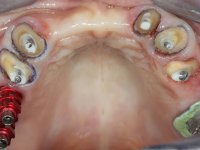

Female patient, 43 years old non-smoker. After a clinical and imaging examination, the patient presented teeth 1.7 / 1.4 / 1.3 / 2.2 / 2.3 / 2.4 / 2.6 with endodontic treatment in the upper jaw, showing absence of teeth 1.6 / 1.5 / 1.2 / 1.1 /2.1 and 2.5, and was rehabilitated with a 10-element monobloc metal-ceramic bridge. The anterior maxilla presented extensive vertical and vestibular bone reabsorption. In the lower jaw, two implants were placed at the site of teeth 4.6 and 4.5 rehabilitated with a metal-ceramic bridge. Teeth 3.6 and 3.7, with endodontic treatment, were rehabilitated with intra-radicular posts and a two-element metal-ceramic bridge. The antero-inferior teeth presented class III and IV resin restorations. Tooth 3.5 was absent. The patient had a vertical dimension of occlusion reduction, accompanied by accentuated dental wear and some ceramic fractures. Good oral hygiene.

Alginate impressions were made at both arches arcades, accompanied by intermaxillary registration relations and collecting information with facial bow facial bow. In the laboratory, a provisional bridge with 13 elements in autopolymerizable acrylic was built, in which a metallic reinforcement was included. Teeth 1.7 / 1.4 / 1.3 / 2.2 / 2.3 / 2.4 and 2.6 were used as pillars. The metal-ceramic bridge was removed after performing longitudinal cuts with diamond burs. The dental abutments were reprepared and the temporary bridge was relined in the mouth with self-curing acrylic. After confection of the provisional bridge, a gingival epithesis was made using composite resin with gingival tonality in order to function as a mock-up, which allowed the patient to preview the possibility of using gingiva shade ceramics in the final work. This option was approved by the patient. Subsequently, the placement of two implants in the first quadrant was planned and executed. The provisional monoblock was removed for placement of the implants, and after surgery was again cemented provisionally. After the osseointegration period, the impressions were made to the maxilla. In the anterior zone, impregnated gingival retraction cords were used, and in the posterior areas, kaolin paste was used. Implant printing utilized the open tray technique. The printing material used was soft and regular putty addition silicone, both fast-setting. In the laboratory, the model of provisional restorations and the gingiva epithesis mock-up served as orientation for waxing the infrastructure. The plaster work model and the waxing of the infrastructure were placed in a laboratory scanner and yielded a digital work model, in which the scanning of the waxed infrastructure was superimposed. This overlay facilitated the CAD design of the Zr infrastructure. Subsequently, the CAD drawing for a CAM milling process provided the Zr pieces. The infrastructure was pigmented with a pinkish coloration, which favors the subsequent placement of gum shade ceramic. During the modeling of the infrastructure, the need to increase the occlusal wear on tooth 1.4 was detected. This was done in the real working model cast and an acrylic wear control guide was created, which accompanied the proof of the infrastructures. Corrective wear and Zr parts test were performed in mouth. During the test, the color choice of the gum shade ceramic was reassessed. The treatment was finished in the laboratory, and after approval by the patient, was definitively placed in the mouth.